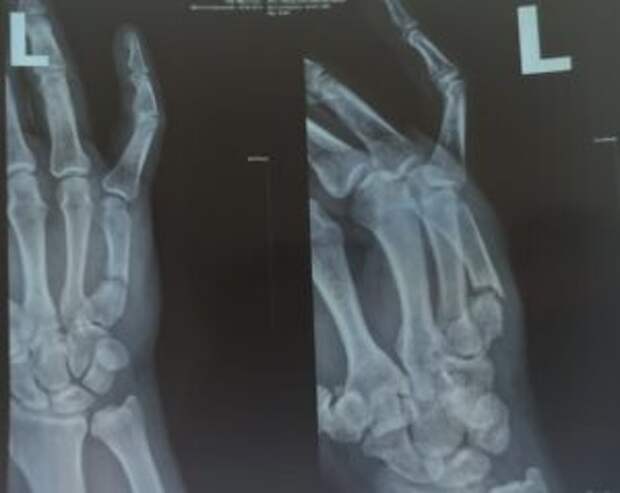

Am Montag, dem 07.03.22, kommt der erste Verletzte zur Behandlung in München an. Hier ist eine Zusammenfassung des Patienten: Diagnose: Schussfraktur des fünften Mittelhandknochens mit Dislokation. Es entstand ein falsches Gelenk, eine Operation ist erforderlich. Aufnehmendes Krankenhaus: Universitätsklinikum Rechts der Isar.

Diagnose: Schussfraktur des fünften Mittelhandknochens mit Dislokation. Es entstand ein falsches Gelenk, eine Operation ist erforderlich.